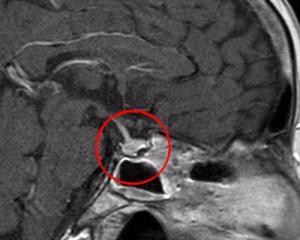

Для диагностики пациентам назначаются консультации специалистов: эндокринолога, офтальмолога, нейрохирурга и онколога, которые имеют опыт в данной области. Затем проводится инструментальное обследование, включающее:

- МРТ головы;

- рентгенокраниографию в двух проекциях;

- пневмоцистернографию;

- компьютерную томографию;

- микроскопическое исследование биопсийного материала;

- церебральную ангиографию.

- Магнитно-резонансная томография (МРТ): Это основной метод визуализации, который позволяет получить детальные изображения гипофиза и окружающих тканей. МРТ помогает определить размер опухоли, её локализацию и влияние на соседние структуры, такие как зрительные нервы.

- Компьютерная томография (КТ): Используется реже, но может быть полезна в случаях, когда МРТ невозможно провести. КТ позволяет выявить кальцификации в опухоли и оценить её размеры.